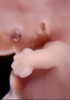

Carnegie Stage 18 (44 post-ovulatory days)

Most embryos at stage 18 are approximately 44 postovulatory days old and measure 13-17 mm in length. Distinguishing criteria for this stage include cervical and lumbar flexures, distinct notching in the hand plate, the first appearance of the elbow, eyelid folds may appear in more advanced specimens, and auricular hillocks begin to form distinct parts of the external ear.